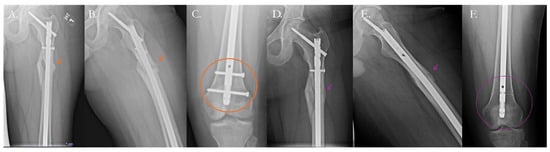

4.2.1. Traditional Surgical Approaches

4.2.2. Surgical Solutions with Biologic Therapy